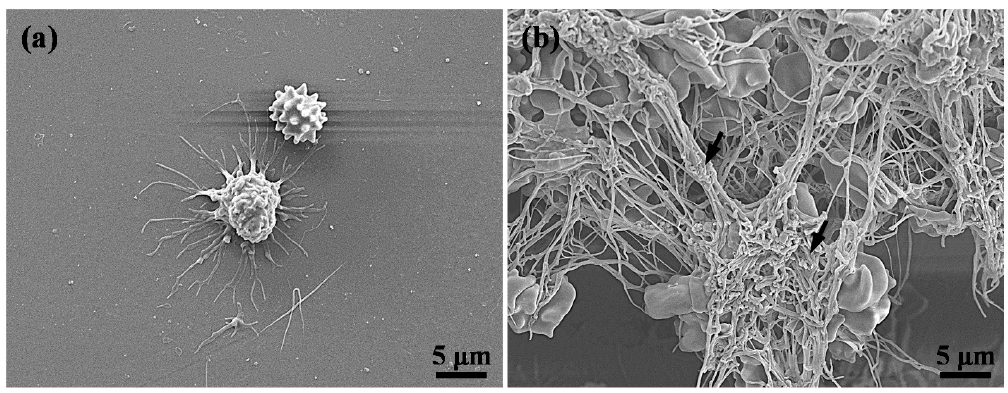

3.4. Hemocompatibility of the Investigated Implants